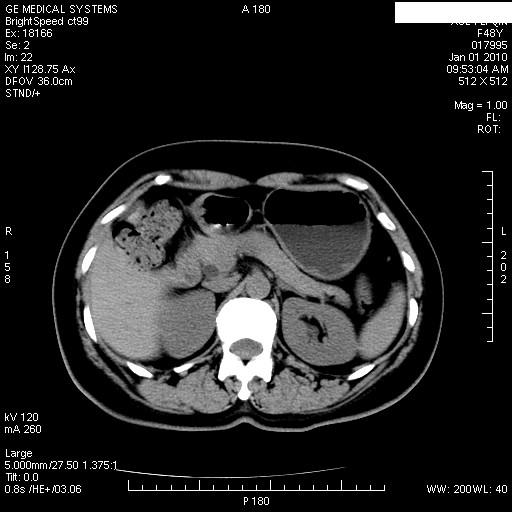

患者女性 48岁 突发上腹部疼痛,无其他不适,查体莫菲氏征阴性,ct示:胆囊炎,胆总管上端轻度扩张

图片如下:

经过抗炎解痉镇痛治疗一周后复查ct如下: